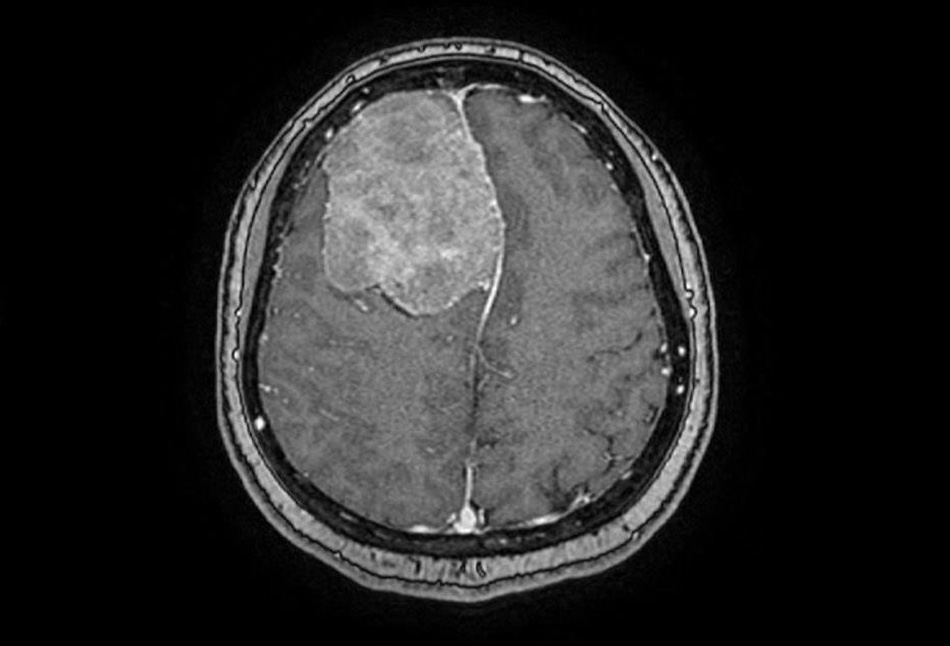

Chị Trịnh Nhật Khánh (nữ võ sư 45 tuổi, sống tại TP.HCM) thỉnh thoảng bị đau đầu nhẹ nên quyết định đi tầm soát đột quỵ tại Bệnh viện FV. Kết quả chụp MRI đã bất ngờ phát hiện ra một khối u màng não rất to, đường kính hơn 6cm, nhìn như một trái cam chèn ép gần ¼ não.

Phim chụp MRI cho thấy một khối u lớn như trái cam sành trong não phải bệnh nhân

“Khối u phát triển trong thời gian dài, hộp sọ thích nghi với khối u nên khó được phát hiện. Khối u chưa ảnh hưởng tới chức năng thần kinh cấp cao, dù bệnh nhân thỉnh thoảng bị đau đầu. Tuy nhiên, trường hợp này cần được mổ sớm, vì nếu khối u lớn hơn nữa có thể gây ra các biến chứng nguy hiểm như động kinh hoặc thậm chí đe dọa trực tiếp đến tính mạng bệnh nhân”, BS.CKII Trần Lương Anh – Trưởng khoa Ngoại Thần kinh và Cột sống, nhận định.